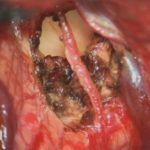

498

'23年12月

20代

下垂体卒中

頭蓋内腫瘍摘出術

No.’23_132 摘出 前

No.’23_132  摘出 中

No.’23_132 摘出 後